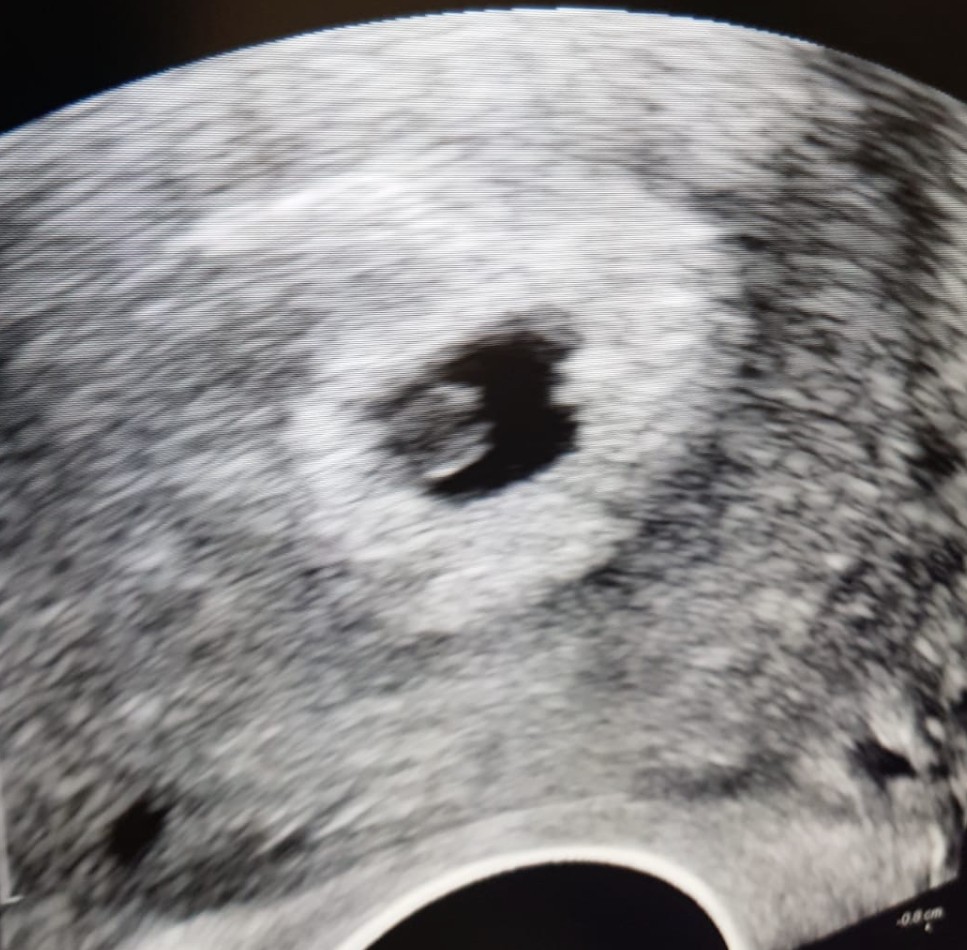

Booooże dziewczyny co my dzisiaj przeżyliśmy 🤦🏼‍♀️🤦🏼‍♀️🤦🏼‍♀️🤦🏼‍♀️

Miałam plamienia od czwartku, malutkie bo malutkie ale były. W niedziele wieczorem zobaczyłam krew, normalnie ze mnie wyleciało pare kropel. Nooo i tylko w głowie - to koniec. Brzuch bolał jak na okres a nawet może więcej.

Mąż oczywiście nie panikuj, będzie dobrze. Był akurat czas do spania, więc spałam jak spałam, cały czas zaglądałam w majty :/

Ale w nocy nic oprócz luteiny nie było.

Uspokoiłam się trochę.. ale jak rano w łazience wyleciała ze mnie jakaś galaretka mniej więcej 1 cm to już wiedziałam, że to koniec. Cały dzień przeryczalam.. zrobiłam betę, progesteron i estradiol ale oczywiście nie mam jeszcze wyników.

W końcu pod wieczór pojechaliśmy do szpitala, żeby mieć czarno na białym, że to koniec. Ale tam czekała na nas niespodzianka ❤️ Nasz kochany kropeczek był i ma się dobrze, serduszko bije. Płakaliśmy jak dzieci, zresztą nadal płacze ale już ze szczęścia ;)

Już wiem, że będzie to rojber 😍

• 7E957215-F686-405E-A0A2-6E9A5ADB1EAD.jpeg

7E957215-F686-405E-A0A2-6E9A5ADB1EAD.jpeg

170,6 KB · Wyświetleń: 89